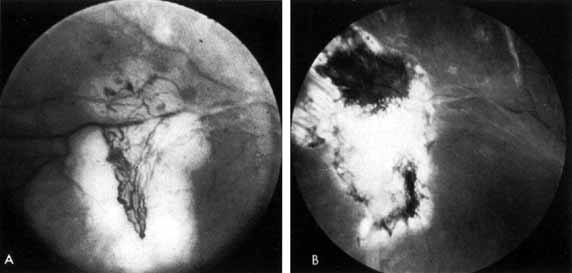

Two types of diabetic retinal detachments occur, those that are caused by traction alone (nonrhegmatogenous) (Fig. 14), and those caused by retinal break formation (rhegmatogenous) (Figs. 15 and 16). Characteristics of nonrhegmatogenous (traction) detachment in PDR include the following: (1) the detached retina is usually confined to the posterior fundus and infrequently extends more than two-thirds of the distancd to the equator, (2) it has a taut and shiny surface, (3) it is concave toward the pupil, and (4) there is no shifting of subretinal fluid.

Fig. 14 Traction retinal detachment. The detached retina has a smooth noncorrugated appearance and is convex toward the pupil.

Fig. 15 Combined traction/rhegmatogenous retinal detachment. The detached retina has a corrugated appearance and is concave toward the pupil.

Fig. 16 Round hole near fibrous proliferation.

In combined traction/rhegmatogenous detachment, the borders of the elevated retina usually extend to the ora serrata; the retinal surface is dull and grayish and undulates because of retinal mobility caused by shifting subretinal fluid. The causative retinal breaks are usually found in the posterior pole near areas of fibrovascular proliferation. They are oval in shape and appear to be partly the result of tangential traction from the proliferative tissue as well as vitreous traction. Determining the location of retinal holes may be complicated by many factors, particularly poor dilation of the pupil, lens opacity, increased vitreous turbidity, vitreous hemorrhage, intraretinal hemorrhage, and obscuration of the breaks by overlying proliferative tissue. Often they are only located during vitrectomy surgery.